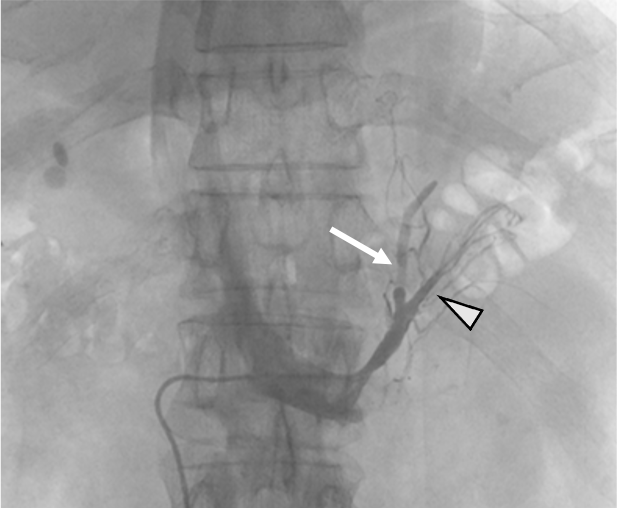

高血圧, 低K血症の精査で左副腎腫瘤が指摘され, 負荷試験の結果, 原発性アルドステロン症の診断となった, 副腎静脈サンプリング前に,プランニング目的のCTが施行された, その後の副腎静脈サンプリングでは, 左副腎からの片側性のアルドステロン過剰分泌が認められ, 手術の方針となった.

原発性アルドステロン症は, 治癒可能な二次性高血圧であり, 本態性高血圧より脳・心血管, 腎合併症の頻度が高く, その診断および治療の重要性が指摘されている, 片側性のアルドステロン症の場合, 外科的切除によりアルドステロン過剰の正常化, 高血圧および臓器障害の改善・防止が期待できる, このため, 手術が考慮される場合には副腎静脈サンプリングによる機能的局在診断を行う, 原発性アルドステロン症診療ガイドライン20211)では, この副腎静脈サンプリングの成功率を向上させる方法の一つとして, ダイナミックmulti-detector row CT(MDCT)が推奨されている, MDCTでは, 横断像やMPR(Multi planar Reconstruction)を用いて, 副腎静脈の走行やvariationの確認などを行うが, これに加え当院では,仮想透視画像を作成し, 右副腎静脈の下大静脈開口部のレベルや, 副肝静脈との位置関係など, 立体的な解剖学的把握を行っている, その結果, サンプリング時に, スムーズかつ的確なカテーテル操作が可能となる.

本検査における後期動脈相は, 右副腎静脈と下大静脈との合流部, また左副腎静脈と下横隔静脈, 腎静脈との合流部の形態評価が求められる重要な撮影時相である. そのため30sec注入時間固定法とbolus tracking法の併用を行い, 腹部下行大動脈において+100HUのCT値上昇をトリガーとし, 20secのdelay timeにて後期動脈相の撮影を行っている. その後の門脈優位相は, トリガーから40secの撮影とし, 主に副肝静脈と下大静脈との合流部の形態評価が目的とされる. 造影コントラスト向上のため. 可能な限り低管電圧撮影が行えるよう留意している. なお, 本症例は, 造影剤量がプロトコルより少ない症例であったが, 低管電圧撮影や後期動脈相の最適な撮影タイミングにより, 副腎静脈を良好に描出し得た.